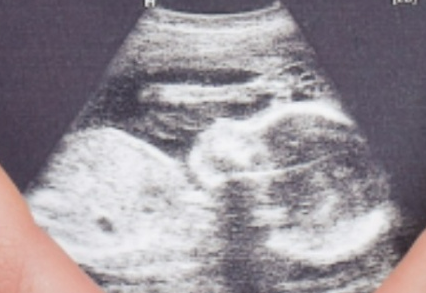

监测排卵,做B超,然后降调、打针、取卵、吃药、打黄体酮、移植、抽血验孕,一切都很顺利,试管让我成功的成为了母亲。